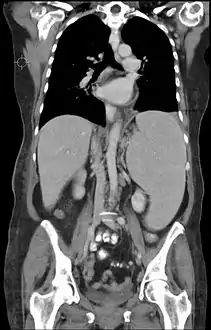

![]() تصوير مقطعي محوسب يظهر فيه طَحَل لدى مريض يعاني من ابيضاض لمفاوي مزمن تصوير مقطعي محوسب يظهر فيه طَحَل لدى مريض يعاني من ابيضاض لمفاوي مزمن | |